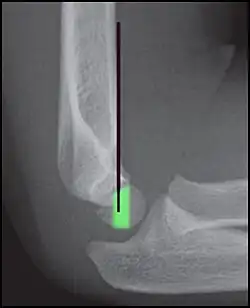

Anterior humeral line (black line), with normal area passed on the capitulum of the humerus colored in green in a 4-year-old child.[9] -

The anterior humeral line is not reliable in children with sparse ossification of the capitulum, such as in this 6 months old child.[9]